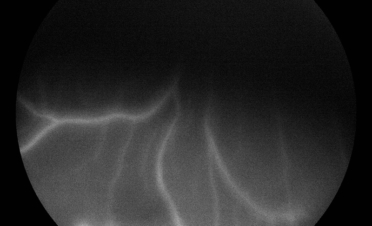

Ante la sospecha de un problema en el segmento posterior del ojo se recomendó la realización de pruebas adicionales que permitieran determinar la causa de su pérdida de visión:

En la angiografía fluoresceínica se apreció hiperfluorescencia del nervio óptico y en la periferia de la retina. Estas imágenes son compatibles con neuritis óptica y coriorretinitis.